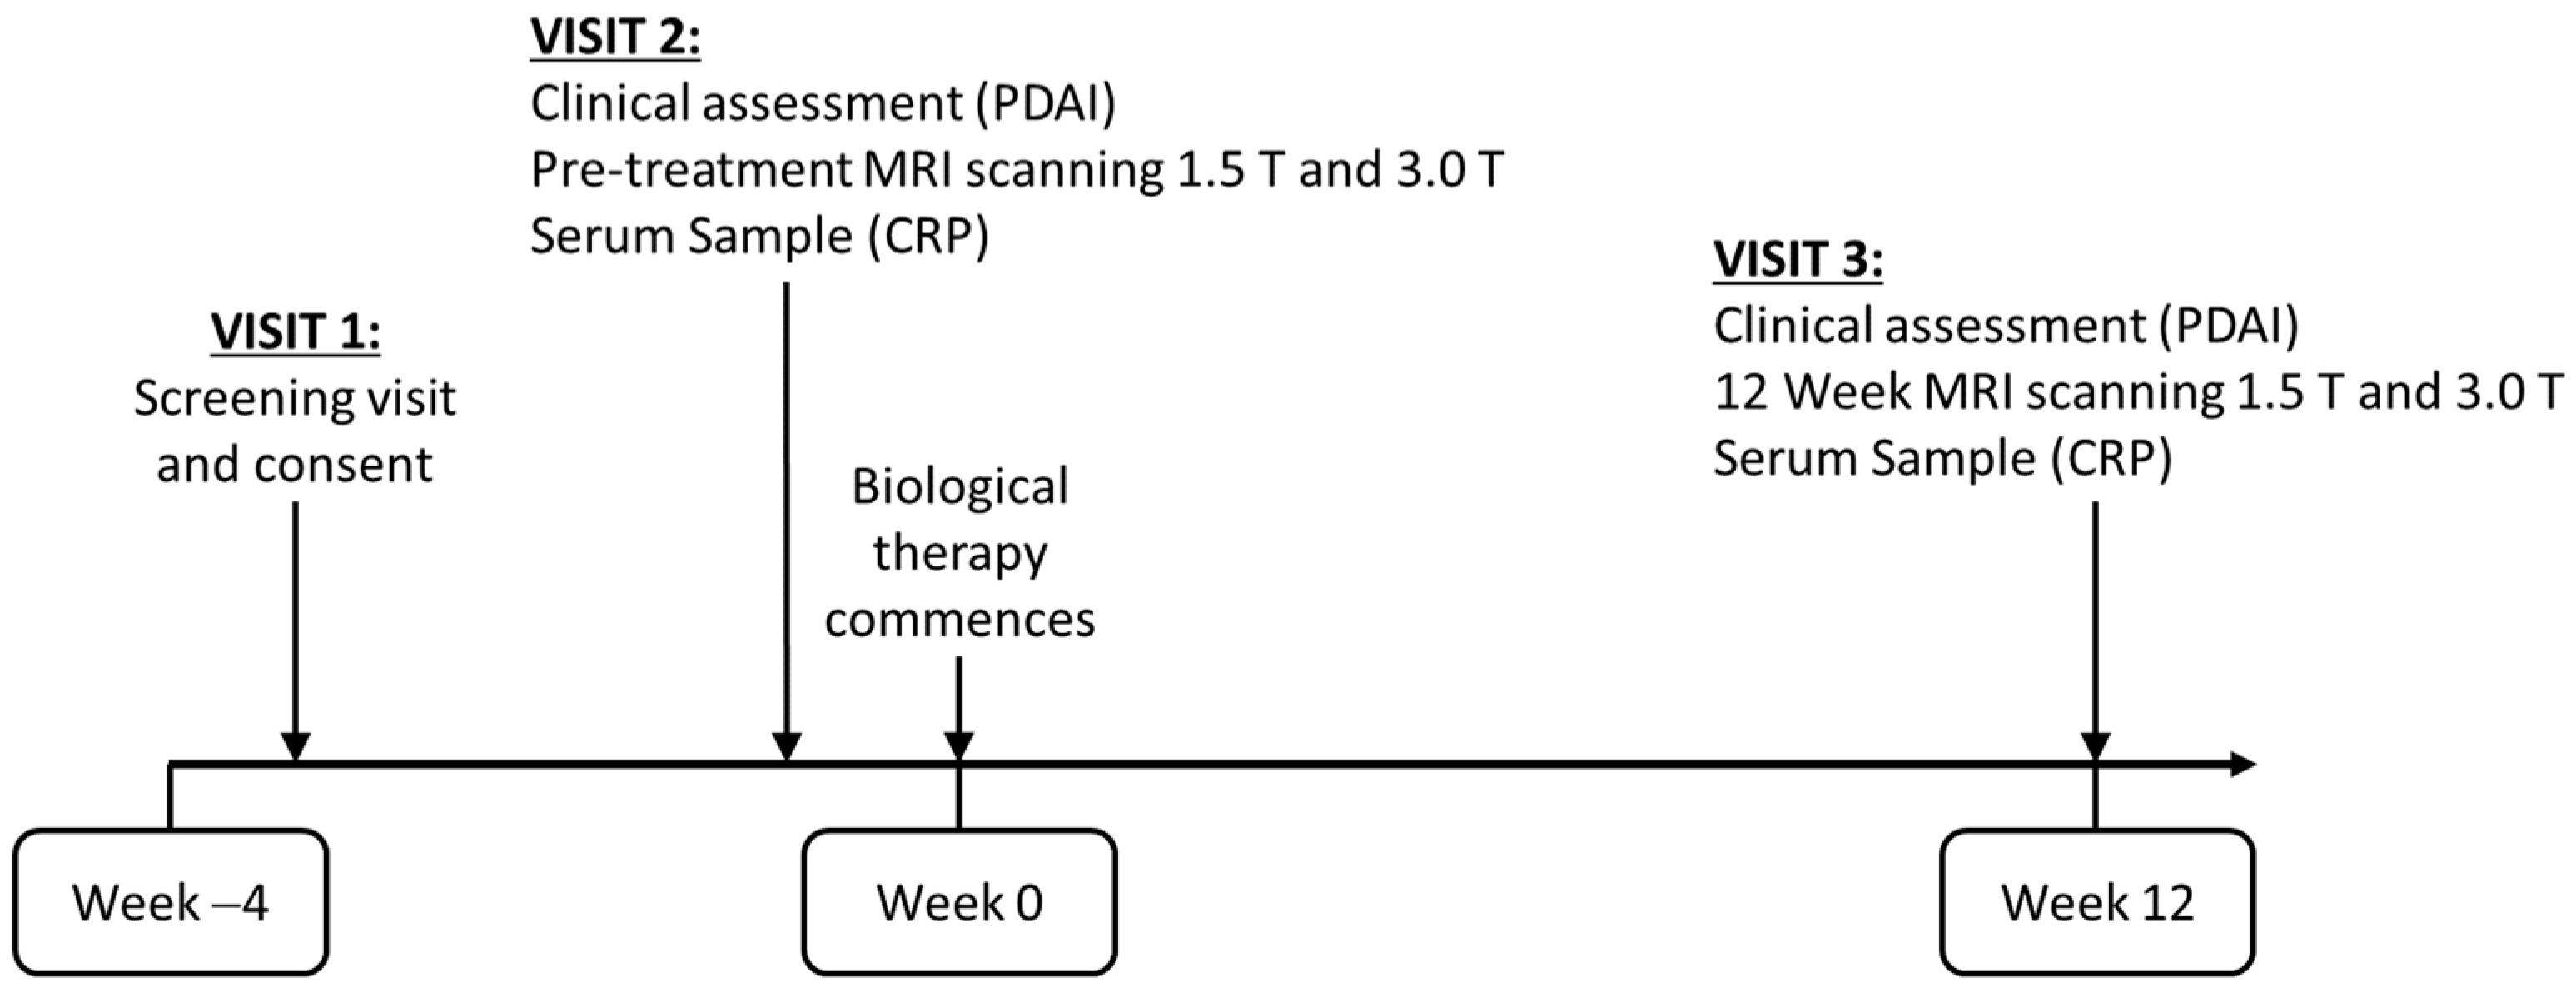

2. Materials and Methods

2.1. Study Population

2.3.2. Repeatability of Quantitative Measurements

2.4. Clinical Evaluation